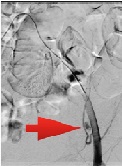

Intraparenchymal Stenting in Blunt Liver Trauma: A Case Report of a Simultaneous Damage-Control and Tissue-Sparing Surgical Technique

Edgar Fernando Hernández-García*, José Lauro Gilberto Delgado-Arámburo, Luis Manuel García-Núñez, Hector F Noyola Villalobos, Fernando Federico Arcaute-Velázquez